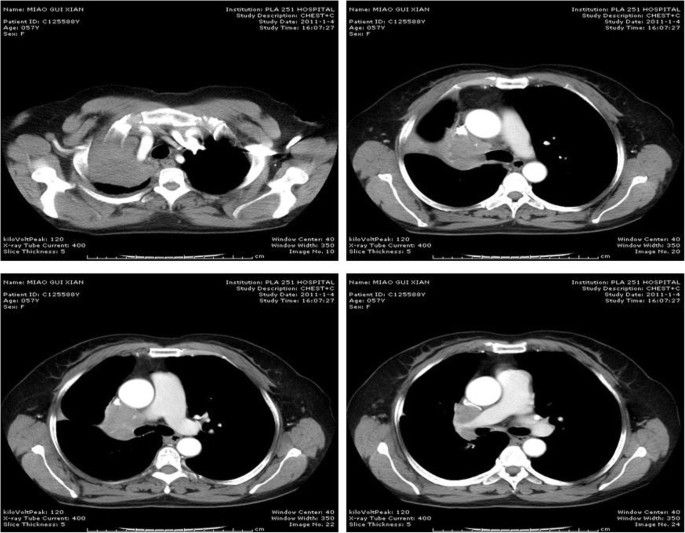

A 52-year-old woman with a 3 month’s history of cough and hemoptysis consulted a nearby clinic. Chest X-ray showed atelectasis of the right upper lobe caused by locally advanced lung cancer with mediastinal invasion. Bronchoscopic biopsy showed squamous cell carcinoma. Chest computed tomorgraphy (CT) showed atelectasis of right upper lobe tumor invasion into the right main pulmonary artery. The SVC was compressed and narrowed but remained patent (Fig. 1). No significantly enlarged mediastinal lymph nodes were seen. Bronchoscopy revealed an exposed tumor in the right upper bronchus which completely obstructed the lumen. Brain and abdominal CT, and bone scintigraphy revealed no signs of distant metastases. On the basis of these findings, the tumor was evaluated to be resectable by intrapericardial pneumonectomy. The surgery was performed through a right thoractomy. The pericardial was opened from SVC to the level of right upper pulmonary vein 2 cm posterior and parallel to the phrenic nerve. The SVC was isolated from the atrium to the brachiocephalic trunk, which involved SVC denudation at the point of its connection with pericardium. Then the right pulmonary artery was dissected and ligated between the ascending aorta and the SVC. The right upper pulmonary vein was ligated intrapericardially. The right lower pulmonary vein was dissected and ligated outside of the pericardium. Finally the right main bronchus was manipulated using a stapler to complete the right pneumonectomy. No direct tumor invasion into the SVC was detected. The lower part of pericardium was closed interruptedly and the upper defect was left open. The chest was drained using an intercostals tube that was kept clamped and released for half an hour the next morning. The patient was transferred postoperatively to Intensive Care Unit, and the tracheal tube was withdrawn 2 h after operation. About 18 h after operation, the patient was transferred to an ordinary room. Immediately after a short period of hard coughing, the patient developed tachycardia arrhythmias, hypotension, followed by loss of consciousness. After resuscitation, the patient was conscious but developed cyanosis of the SVC drainage area, uropenia, and hypotension (80/30 mmHg). She felt more comfortable in the right decubitus position. Emergency bedside-echocardiography showed that the SVC was obstructed due to thrombus formation. Cardiac herniation into the right pneumonectomy space was detected on repeated chest radiography which showed a shift of the heart into right hemithorax (Fig. 2). Rethoracotomy was performed on the second day after the intrapericardial pneumonectomy. At operation it was found that the heart had rotated into the right hemithorax along the axis of the vena cava, and the SVC was strangulated. The heart was placed back into its normal position. The pericardium was torn from its initial incision to cardiac apex for about 8 cm and this was repaired using a Gore Tex patch. About 5 min after the heart was returned to its normal position, the syndrome of SVC disappeared. The postoperative course was uneventful. The patient has been followed up as tumor-free for more than 3 years.